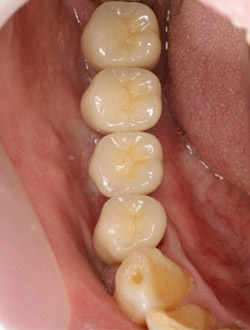

インプラントで噛み合わせの再構成を伴った症例。

治療後のメンテナンスを行わないと

周囲炎になるリスクあり。